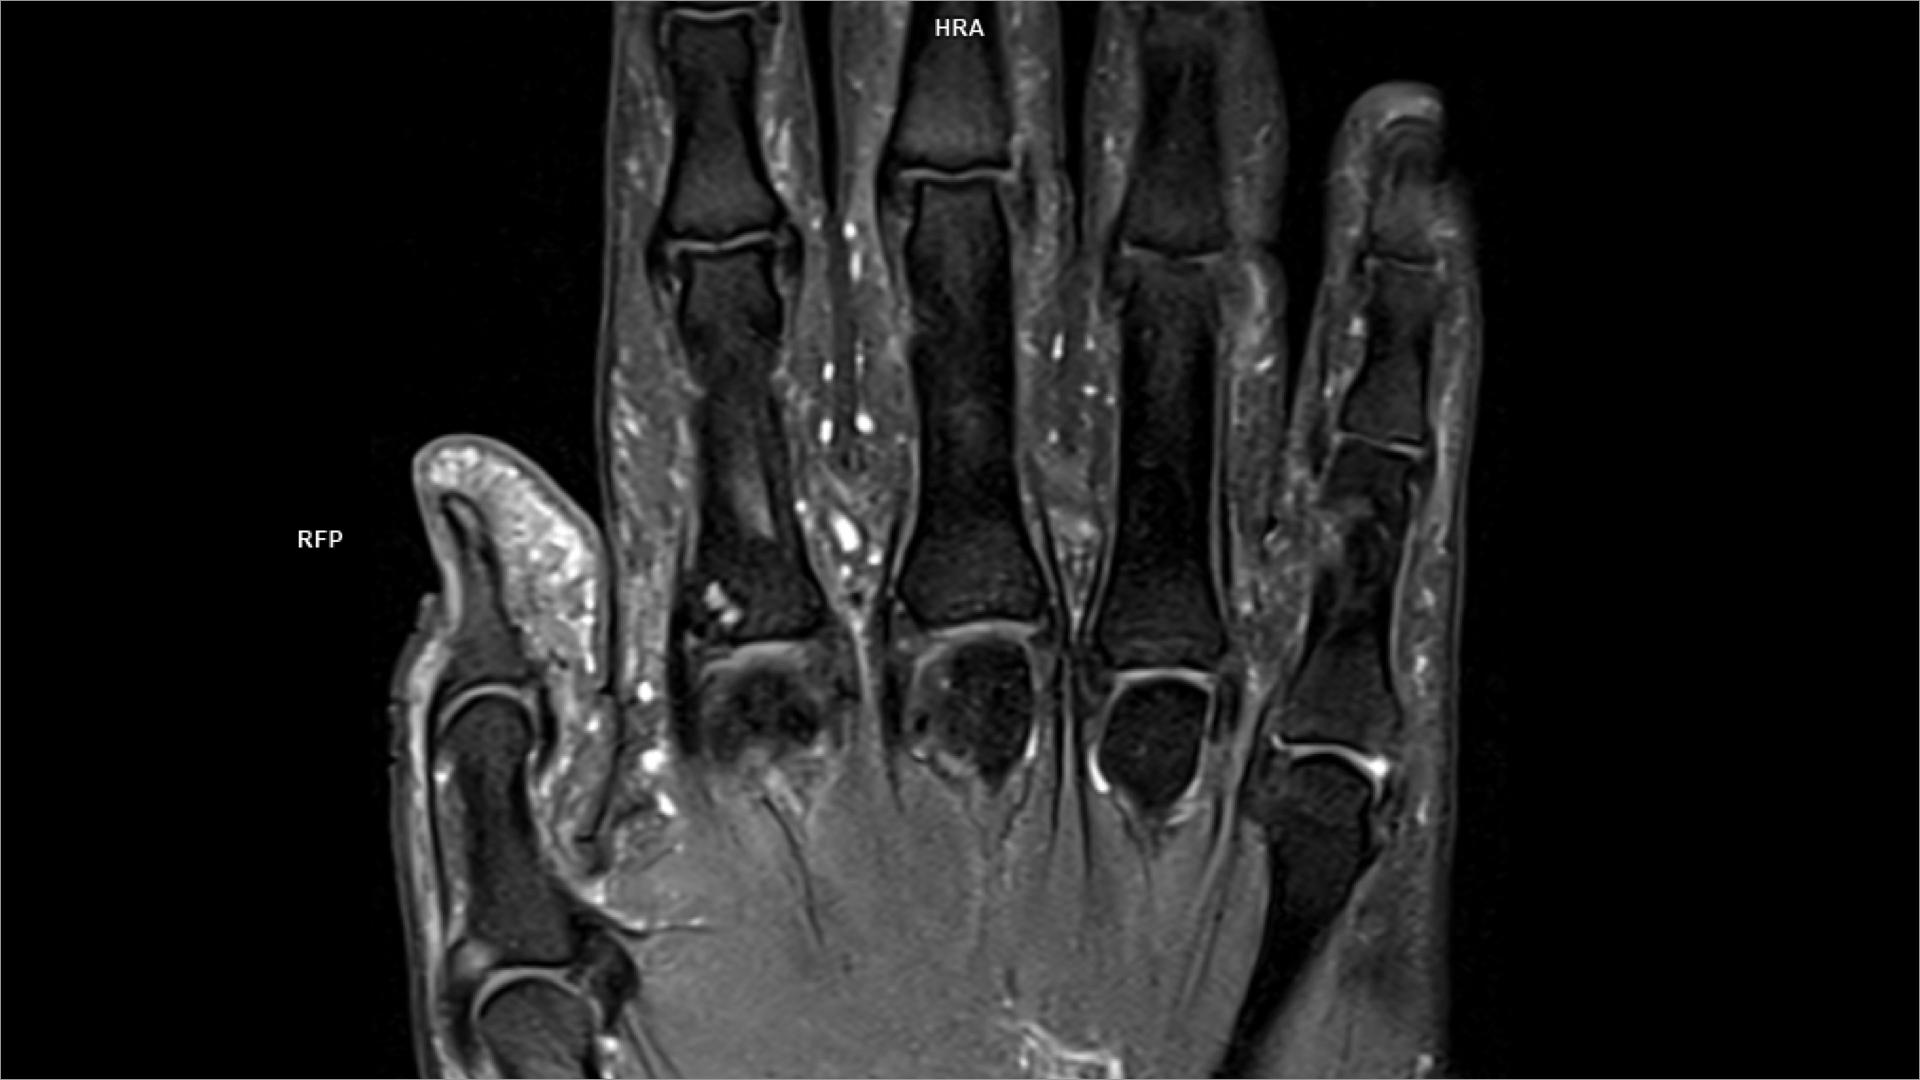

coronal MRI 5 Diagram Quizlet Coronal Pd Mri Rotator cuff tears are the most common cause of shoulder pain and result in loss of strength and loss of stability of the shoulder. The role of mri in. Protocol specifics will vary depending on mri hardware and software, radiologist and referrer preference, patient. In this article we will discuss: Many standard shoulder protocols will include the following fast spin. Coronal Pd Mri.